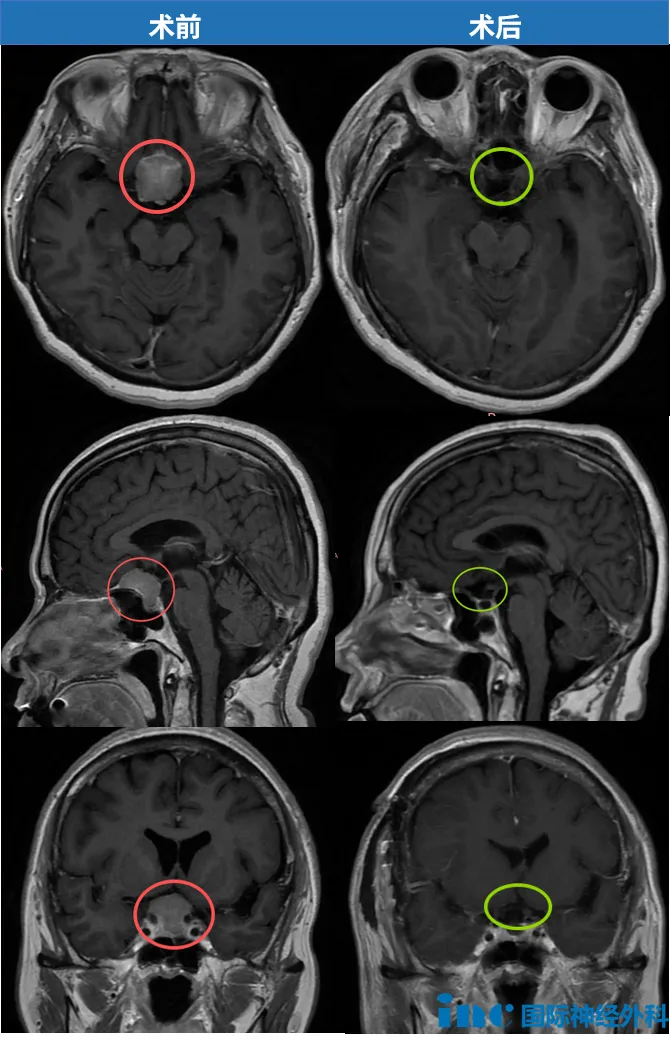

2025年1月9日,手術(shù)當(dāng)天,一家人焦急等候在手術(shù)室外。“一切都好!”當(dāng)聽(tīng)到巴教授說(shuō)出這個(gè)好消息時(shí),家屬也激動(dòng)得連連道謝:“太感謝您了!”

術(shù)后當(dāng)天,陳女士在ICU已能與教授自如交流,視力有所恢復(fù),并于當(dāng)日轉(zhuǎn)入普通病房。這場(chǎng)與時(shí)間的賽跑,他們跑贏了。